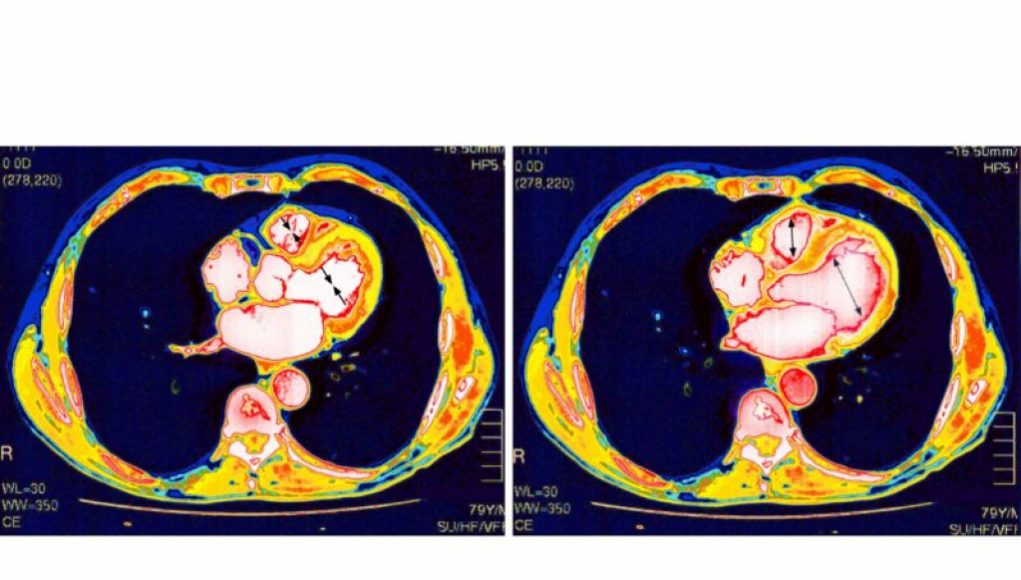

But why do some people develop this complication after vaccination? A new study in Science Immunology provides some fresh insight. The study, led by researchers at Yale University, found that the vaccine is spurring a generalized, vigorous inflammatory response that leads to heart tissue inflammation and damage. The immune systems of these individuals get a little too revved up and over-produce cytokine and cellular responses.

While the study offers a possible answer to the “how,” it doesn’t answer all the questions—including some of the whys, such as why young males? And why the heart? Medical experts don’t know why young males are the most common group to develop myocarditis generally, from any cause. As for why the heart seems to be uniquely damaged, it could be because the heart is constantly working and has limited potential for tissue regeneration, making it more susceptible to inflammation.